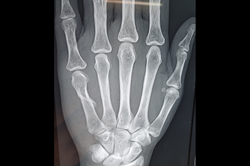

Finger Tip Injury - JESS

Metacarpal Fracture – External Fixator JESS